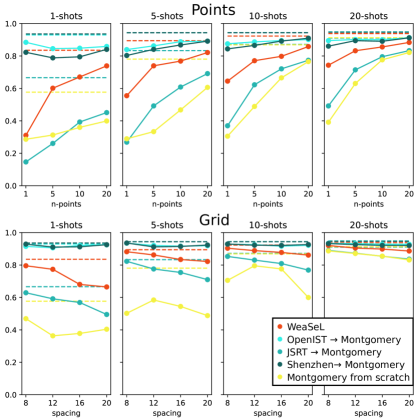

As mentioned in the paper, the results for Montgomery and Shenzhen lungs segmentation task, had results similar to the OpenIST dataset, as can be seen in tables 1 and 2, and in Figure 1. So the same conclusions from the paper holds for these datasets: From Scratch being the worst baseline, Fine Tuning from similar domains providing the best results, while WeaSeL reaching comparable results to the Fine-Tuning baselines with more data samples.

From Scratch From JSRT From OpenIST From Shenzhen WeaSeL Points Points Points Points Points Shot 1 5 10 20 1 5 10 20 1 5 10 20 1 5 10 20 1 5 10 20 1 28.64 31.26 35.99 39.91 15.71 29.78 43.19 49.71 88.42 84.54 84.82 85.89 82.26 78.84 79.49 84.08 43.23 63.28 77.49 78.40 5 28.93 33.34 46.75 60.65 28.92 50.63 63.43 71.06 83.96 86.24 88.79 89.16 80.31 84.09 86.79 89.14 59.67 80.21 81.55 85.26 10 30.52 48.87 66.53 76.56 38.16 64.46 73.88 78.73 87.54 88.69 89.51 90.15 84.38 86.54 89.19 90.97 69.64 78.92 84.54 87.05 20 39.15 63.05 77.65 82.16 52.73 73.82 79.81 83.29 89.48 90.15 90.02 91.33 86.07 89.46 89.07 91.20 74.17 85.01 87.80 89.02 Grid Grid Grid Grid Grid Shot 8 12 16 20 8 12 16 20 8 12 16 20 8 12 16 20 8 12 16 20 1 46.92 36.34 37.81 40.40 62.90 59.17 56.89 49.50 91.50 90.61 92.08 92.45 92.89 91.07 91.23 92.54 87.81 83.72 82.68 78.03 5 50.22 58.43 54.46 48.80 82.28 77.55 75.42 71.00 93.46 92.06 91.64 91.91 93.58 91.18 91.46 92.32 91.74 89.86 88.43 86.12 10 70.54 79.54 77.58 59.96 85.30 83.05 80.90 76.87 92.90 92.54 91.63 92.16 92.94 92.24 92.09 92.62 92.05 91.14 89.93 87.71 20 88.70 87.11 85.47 83.13 88.99 87.27 85.41 83.62 93.40 93.24 92.84 92.78 93.23 92.59 92.12 92.04 92.89 92.14 91.54 90.36